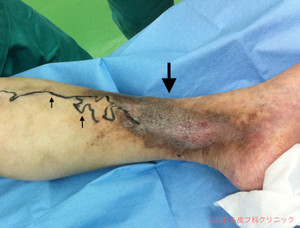

本日の患者さんは、下腿の静脈瘤性潰瘍の方です。潰瘍は保存的に改善しましたが、再発予防のために手術を行いました。

(下写真:↑静脈瘤、↓潰瘍のあったところ)